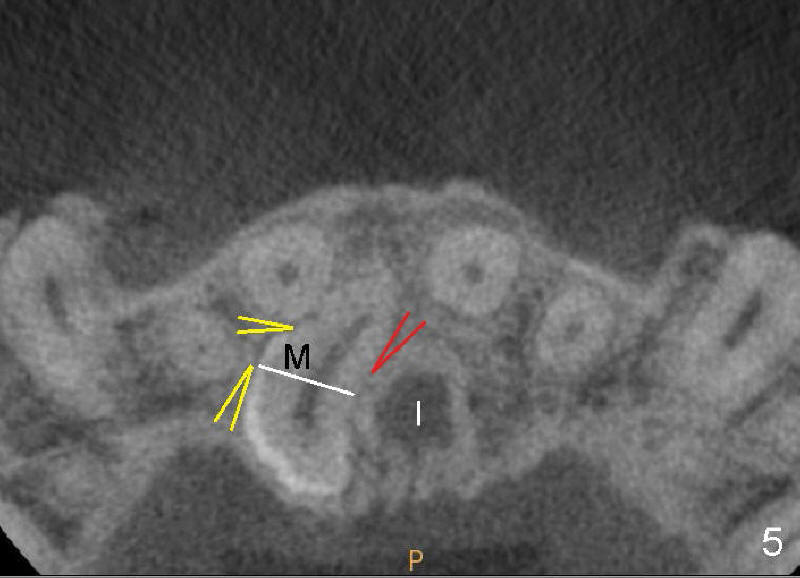

There is no problem to expose the mesiodens palatally with mucoperiosteal flap reflection. But the mesiodens is difficult to be luxated after placement of purchase point lateral to the mesiodens (Fig.5 yellow arrowheads). The supranumerary tooth is sectioned (white line). The coronal portion is easy to be removed, but the radical portion is stable (probably ankylosis). Out of desperation, a purchase point (red arrowhead) is placed between the mesiodens and the incisal canal (I). It helps remove the root, but there is oozing after suturing flap. It seems that the neurovascular bundle is violated when the medial purchase point is made.